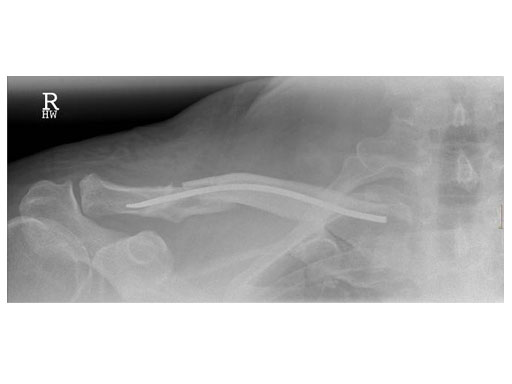

Case 2: 51 years, male, hit by tree

The operative technique as described by Rehm starts with a skin incision just above the sternal end of the clavicle. Approximately one cm lateral to the sternoclavicular joint, a hole is drilled into the anterior cortex. A titanium nail varying in diameter between 2.5 to 3.5 mm is mounted on a universal chuck with T-handle. With oscillating movements the TEN is advanced until it reaches the fracture site. If closed reduction manoeuvres are unsuccessful, an additional skin incision has to be made at the level of the fracture site enabling direct manipulation of the fragments.